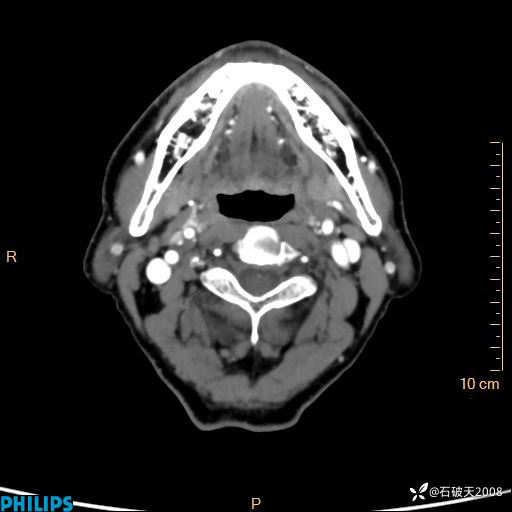

静脉期